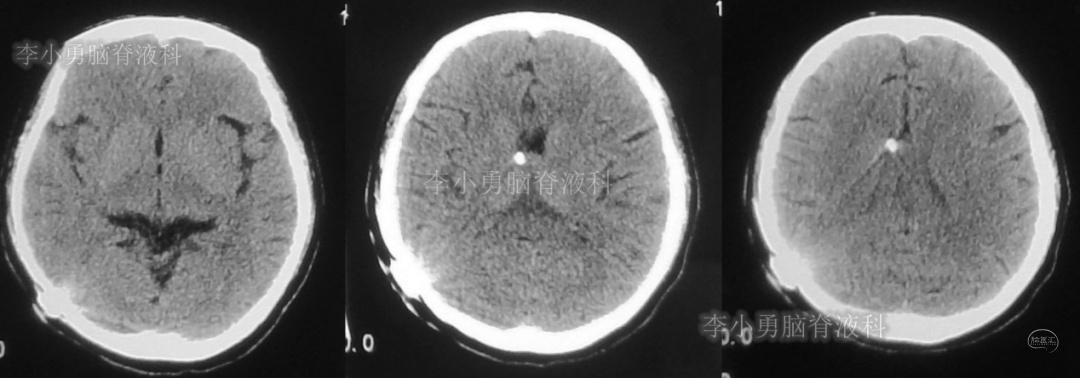

此后1个多月(2019年11月4日到2019年12月16日),患者意识一直无改善,一直呈模糊状态,多次复查头颅CT(图-12至图-20)见脑室大小反复变化不定,医生根据CT结果等反复多次调节分流泵压力(具体过程家属回忆不起)。但患者病情无好转却逐渐加重,逐渐不能咀嚼、吞咽及进食,卧床不起。

图-15:2019年12月3日头颅CT

图-16:2019年12月10日头颅CT

图-17:2019年12月12日头颅CT